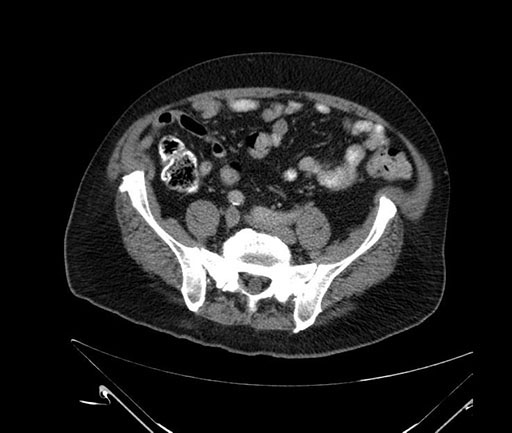

Whipple (pancreaticoduodenectomy) [case 7]

Axial - 3 months prior

Based on your CT findings, which issue(s) would give reason for "planned slowing down moment(s)" in this case?

Considering a standard Whipple procedure, what step(s) of the operation would you do differently in this case?